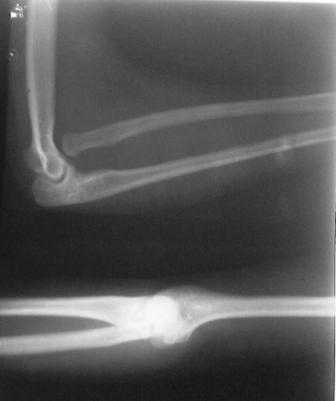

Уважаемые Коллеги! Добрый вечер! Обратилась девушка 18-лет, с жалобами на деформации обоих локтевых суставов, больна с рождения. Оба локтевых сустава в положении сгибания под углом 145гр., дальше разгибание нет за счет укороченных и натянутых м/тканей по передне-наружной поверхности л/сустава. Сгибание полное. но при сгибание предплечья супинируется а при разгибание пронируется,при фиксированным п/плечье ротационных движений нет.Со стороны костно-суставной системы других обл. я патологию не находил. В 2001 г. оперирована лев.рука в одном из центральном институте, со слов вывых был вправлен открыто и фиксация аппаратом Илизарова, после операции рука не сгибалась и ротационных движений не было, что очень ей мещало, после усиленных ЛФК наступило релюксация и движение стало лучше, т.е. как прежная. Фото и Р-снимки прилагается.

Снимки недостаточно информативны ( может быть не все сообщения пришли), рассматривать конфликт проксимального лучелоктевого сочленения невозможно без картинок дистального отдела. Глядя на представленные снимки и предъисторию открытого вправления с рецидивом вывиха, создается впечатление о диспропорции длины локтевой и лучевой костей, врожденном отсутствии аннулярной связи, удерживающей проксимальное лучелоктевое сочленение. Я бы посоветовал сделать снимки предплечья полной длины, включающих дистальное и

проксимальное л.л. сочленения и исходя из этого можно планировать вмешательство: как вариант при обнаружении диспропорции - укорачивающая

остеотомия луча с пластикой связки, если интраоперационно сохраняется тенденция к вывиху.

Врожденный вывих головки лучевой кости является одной из часто встречающихся аномалий локтевого сустава. В большинстве встречаются двухсторонние вывихи и передние.